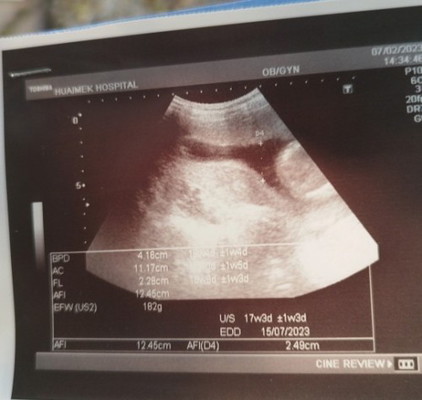

17w+3ค่ะ อยา กทราบว่าเเบบนี้ผิดปกติไหมคะ ไปซาวด์มาเเล้วหมอเห็นอยู่คยเดียวเเต่เรายังงงๆว่าไหนลูกเรา#ท้องเเรก

วันนี้ก้อเพิ่งไปซาวด์มาคะ 17 สัปดาห์เหมือนกัน คุณหมอบอกละเอียดมากคะ ตั้งแต่หน้าตา อวัยวะ หัวใจ แขน ขา

ภาพบางส่วนของน้องหรือเปล่าค่ะ น้องก็มีน้ำหนักแล้ว182g